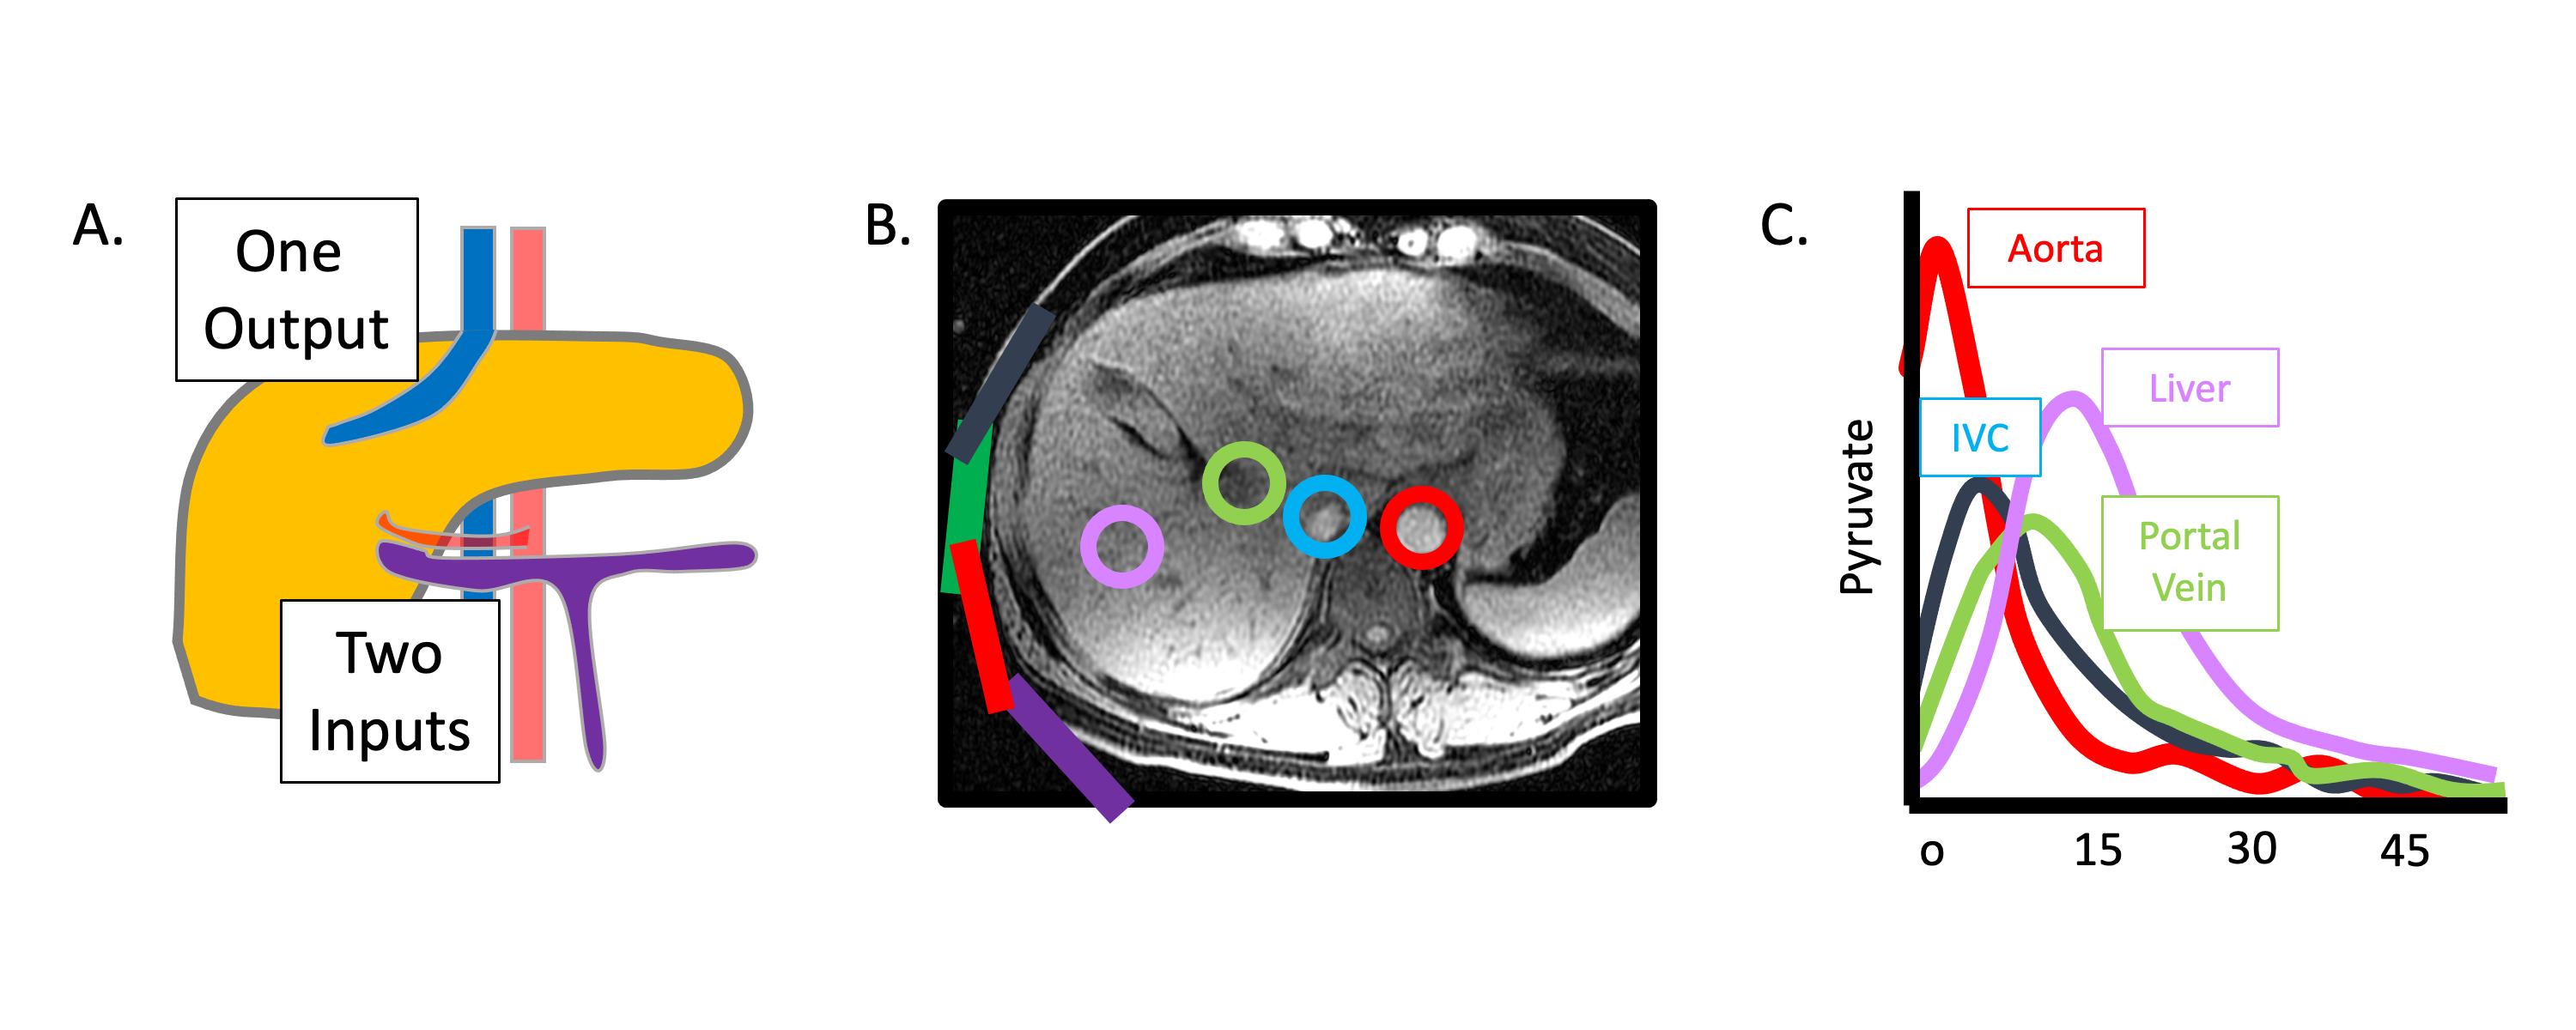

Besides the demanding logistical requirements universally associated with the short signal lifetime of HP magnetization, HP liver imaging presents a unique set of additional technical challenges. As depicted in Figure 1, the dual vascular input to the liver from the portal vein (major source of perfusion) and hepatic artery could complicate the interpretation of signal dynamics. In addition, because HP material in the portal vein has already passed through the GI tract, it could potentially have a different profile than that originating from the hepatic artery. Finally, it is well-known that dramatic alterations in the relative blood flow in the hepatic artery and portal vein can occur with meals, and these changes are further modulated by the presence of superimposed liver diseases such as portal hypertension (7).

Figure 1: Dual blood supply of the liver visualized using HP 13C MRI. (A) Schematic illustration of the blood supply of the liver, showing the portal vein (purple) draining the gastrointestinal tract and the hepatic artery (red), with a single output hepatic vein (blue). (B) T1-weighted image of the liver with ROIs drawn around the aorta (red), inferior vena cava (blue), portal vein (green), and liver parenchyma (purple). (C) HP [1-13C]pyruvate signal measured over time from the vessels shown in (B) demonstrates clear distinct inputs from the arterial and portal venous supply